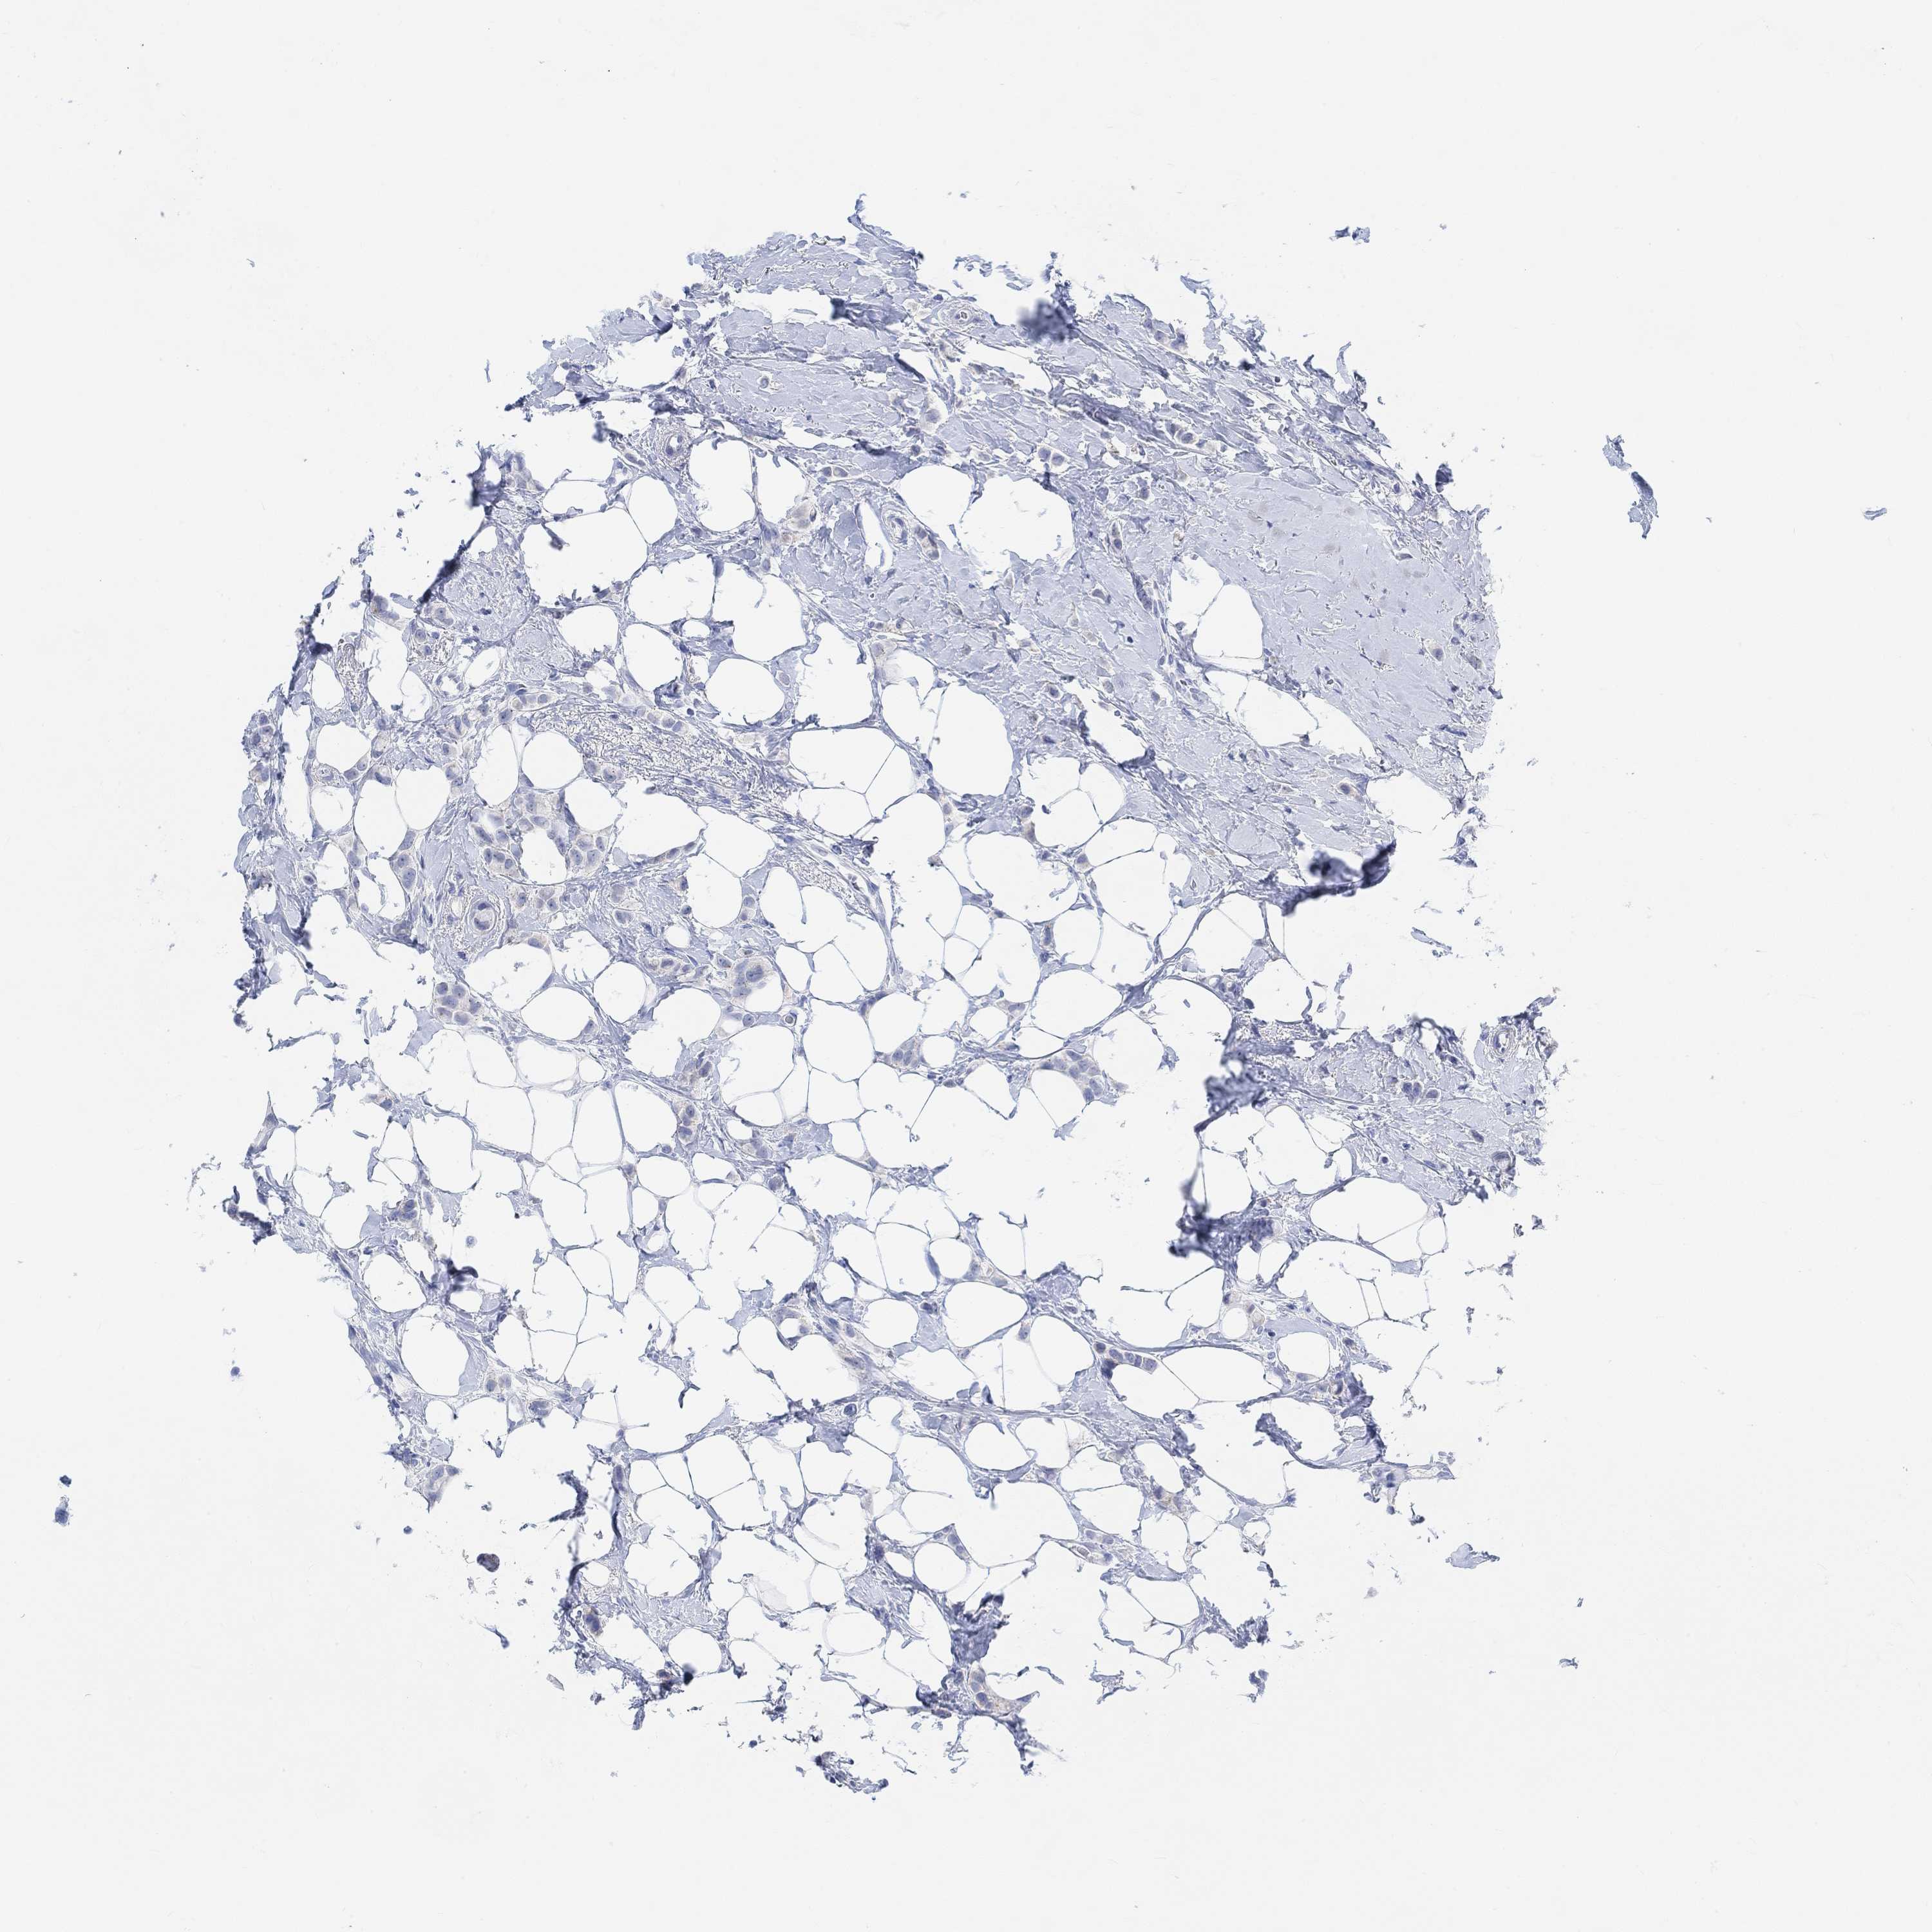

BRCA TCGA BRCA VALIDATION PROTEIN EXPRESSION

ANTIBODIES

AND

VALIDATION